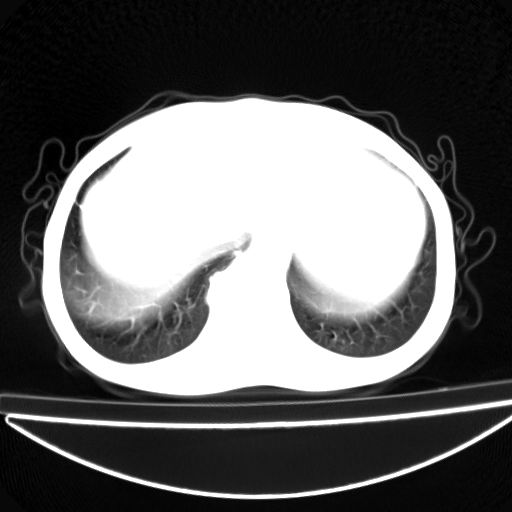

以下是引用杀毒软件在2009-4-28 17:58:00的发言:[br]考虑----左肺慢性肺脓肿形成继发上叶含气不良---抗炎后复查---待排肿瘤所致[br][br][本贴已被 杀毒软件 于 2009-4-28 18:01:26 修改过]